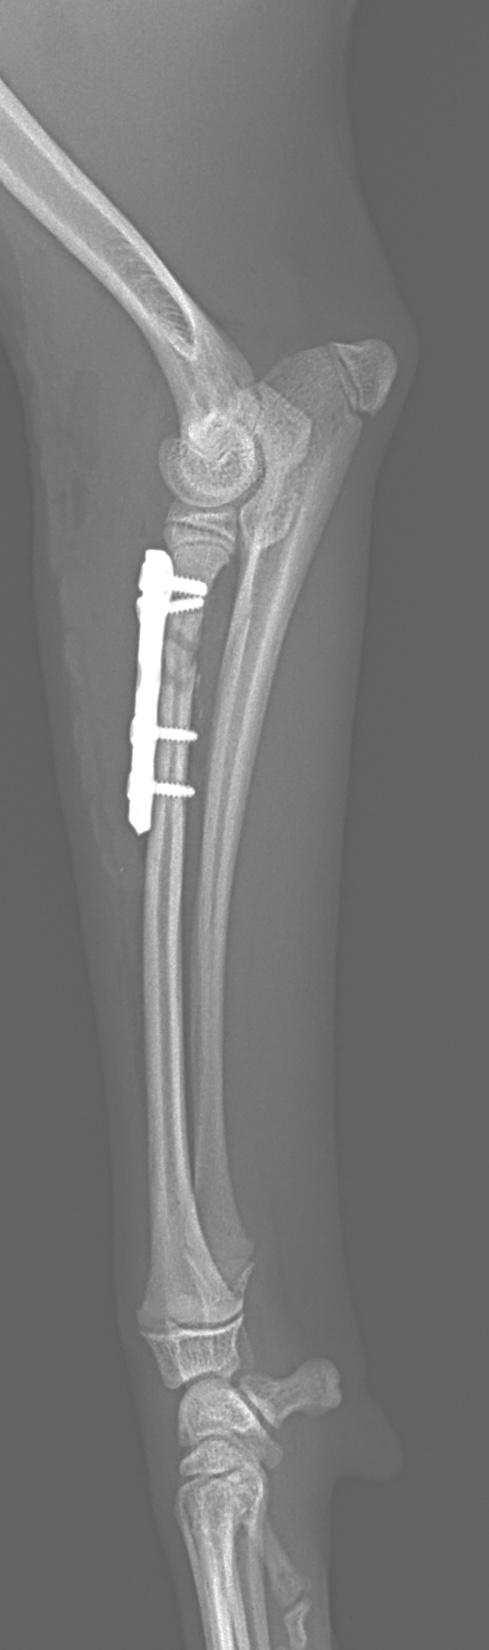

橈骨固定術 #240

Toy Poodleさんがソファーより転落後に橈骨近位を斜骨折したとの事。1.5 Locking Plateで固定術を実施しました。 しばらく安静が必要です。